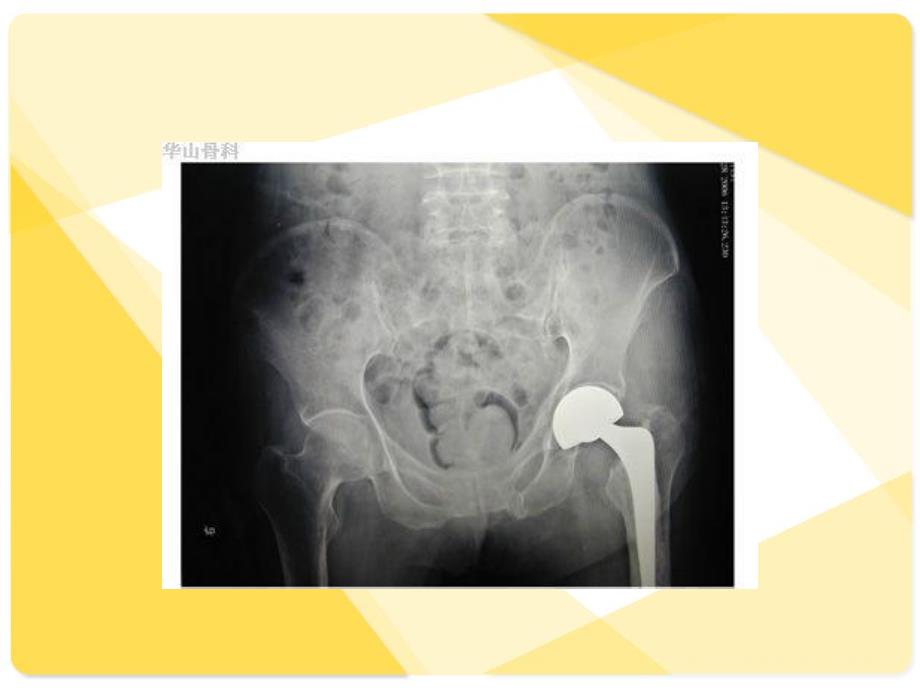

15、旋、伸直位。术后搬动要小心,保持外展、内旋、伸直位。患肢外展中立位牵引患肢外展中立位牵引12周,防止内收、外旋以周,防止内收、外旋以免脱位。以后改用矫正鞋于同样体位免脱位。以后改用矫正鞋于同样体位23周。周。n 2.术后应用抗生素。术后应用抗生素。n 3.有效的负压吸引极为重要,主要为防止感染,有效的负压吸引极为重要,主要为防止感染,又可观察和记录引流液颜色的改变及引流量。引又可观察和记录引流液颜色的改变及引流量。引流管留置不应超过流管留置不应超过72小时,小时,24小时引流量少于小时引流量少于20ml后才可拔管。后才可拔管。n 4.下地前常规拍下地前常规拍X线片,检查人工股骨头在髋臼内线片,

16、检查人工股骨头在髋臼内的位置,也便于术后随诊比较。的位置,也便于术后随诊比较。术后处理n 5.术后应即活动未固定的关节,作肌肉收缩锻炼,下肢按摩,以防深术后应即活动未固定的关节,作肌肉收缩锻炼,下肢按摩,以防深静脉栓塞。静脉栓塞。23日后可起坐,逐渐增大主动和被动范围;术后日后可起坐,逐渐增大主动和被动范围;术后10日日拆线;术后拆线;术后34周可持拐下地。半年内应在持拐保护下行走,锻炼过周可持拐下地。半年内应在持拐保护下行走,锻炼过程可辅以理疗。弃拐后仍应注意避免过度活动和损伤。如有疼痛、局程可辅以理疗。弃拐后仍应注意避免过度活动和损伤。如有疼痛、局部炎症等出现应及时随诊治疗。用生物学固定的病人,在术后部炎症等出现应及时随诊治疗。用生物学固定的病人,在术后6周内周内宜在床上锻炼,以便骨组织长入表面微孔。然后再持拐由不负重而逐宜在床上锻炼,以便骨组织长入表面微孔。然后再持拐由不负重而逐渐加大负重行走。总之,节制负重要时刻注意。渐加大负重行走。总之,节制负重要时刻注意。n 6.严格定期随诊每严格定期随诊每23个月个月1次,以便指导锻炼。定期摄次,以便指导锻炼。定期摄X线片检查,线片检查,